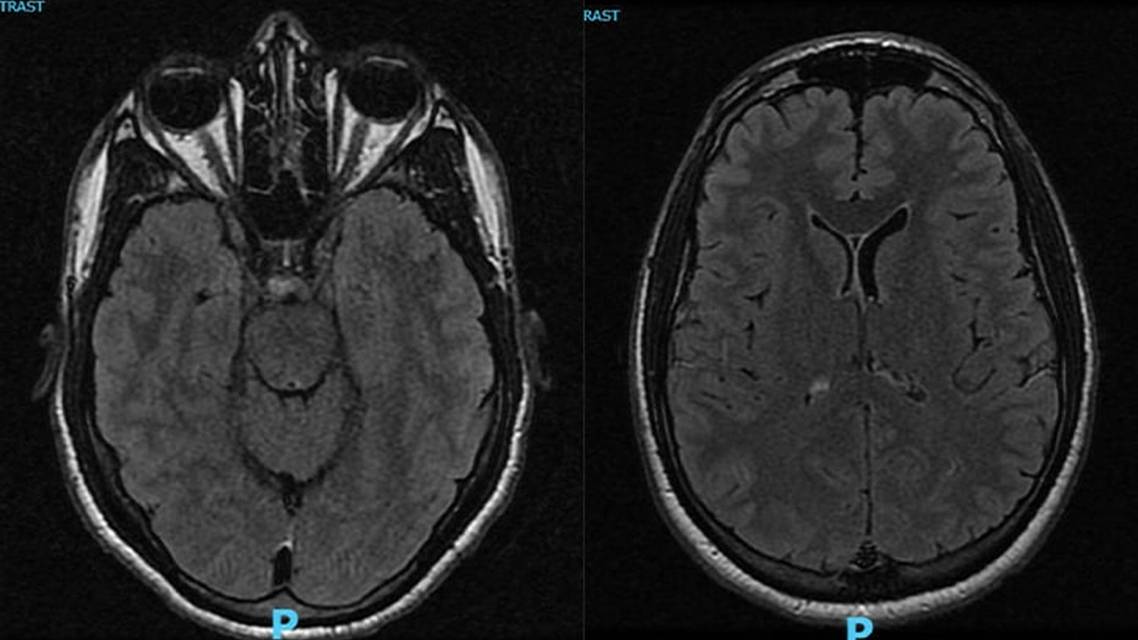

At the time of follow-up 5 days after the CO exposure, neurologic and ophthalmologic examination results remained normal, and no interval difficulties with memory or vision were reported. MRI scans of the brain and orbits showed no areas of diffusion restriction or abnormal T2 signal change (Figure). A 2 mm hypoenhancing sellar mass was discovered incidentally on the brain MRI scan. Imaging of the orbits demonstrated that the optic nerves were normal in size and signal intensity.